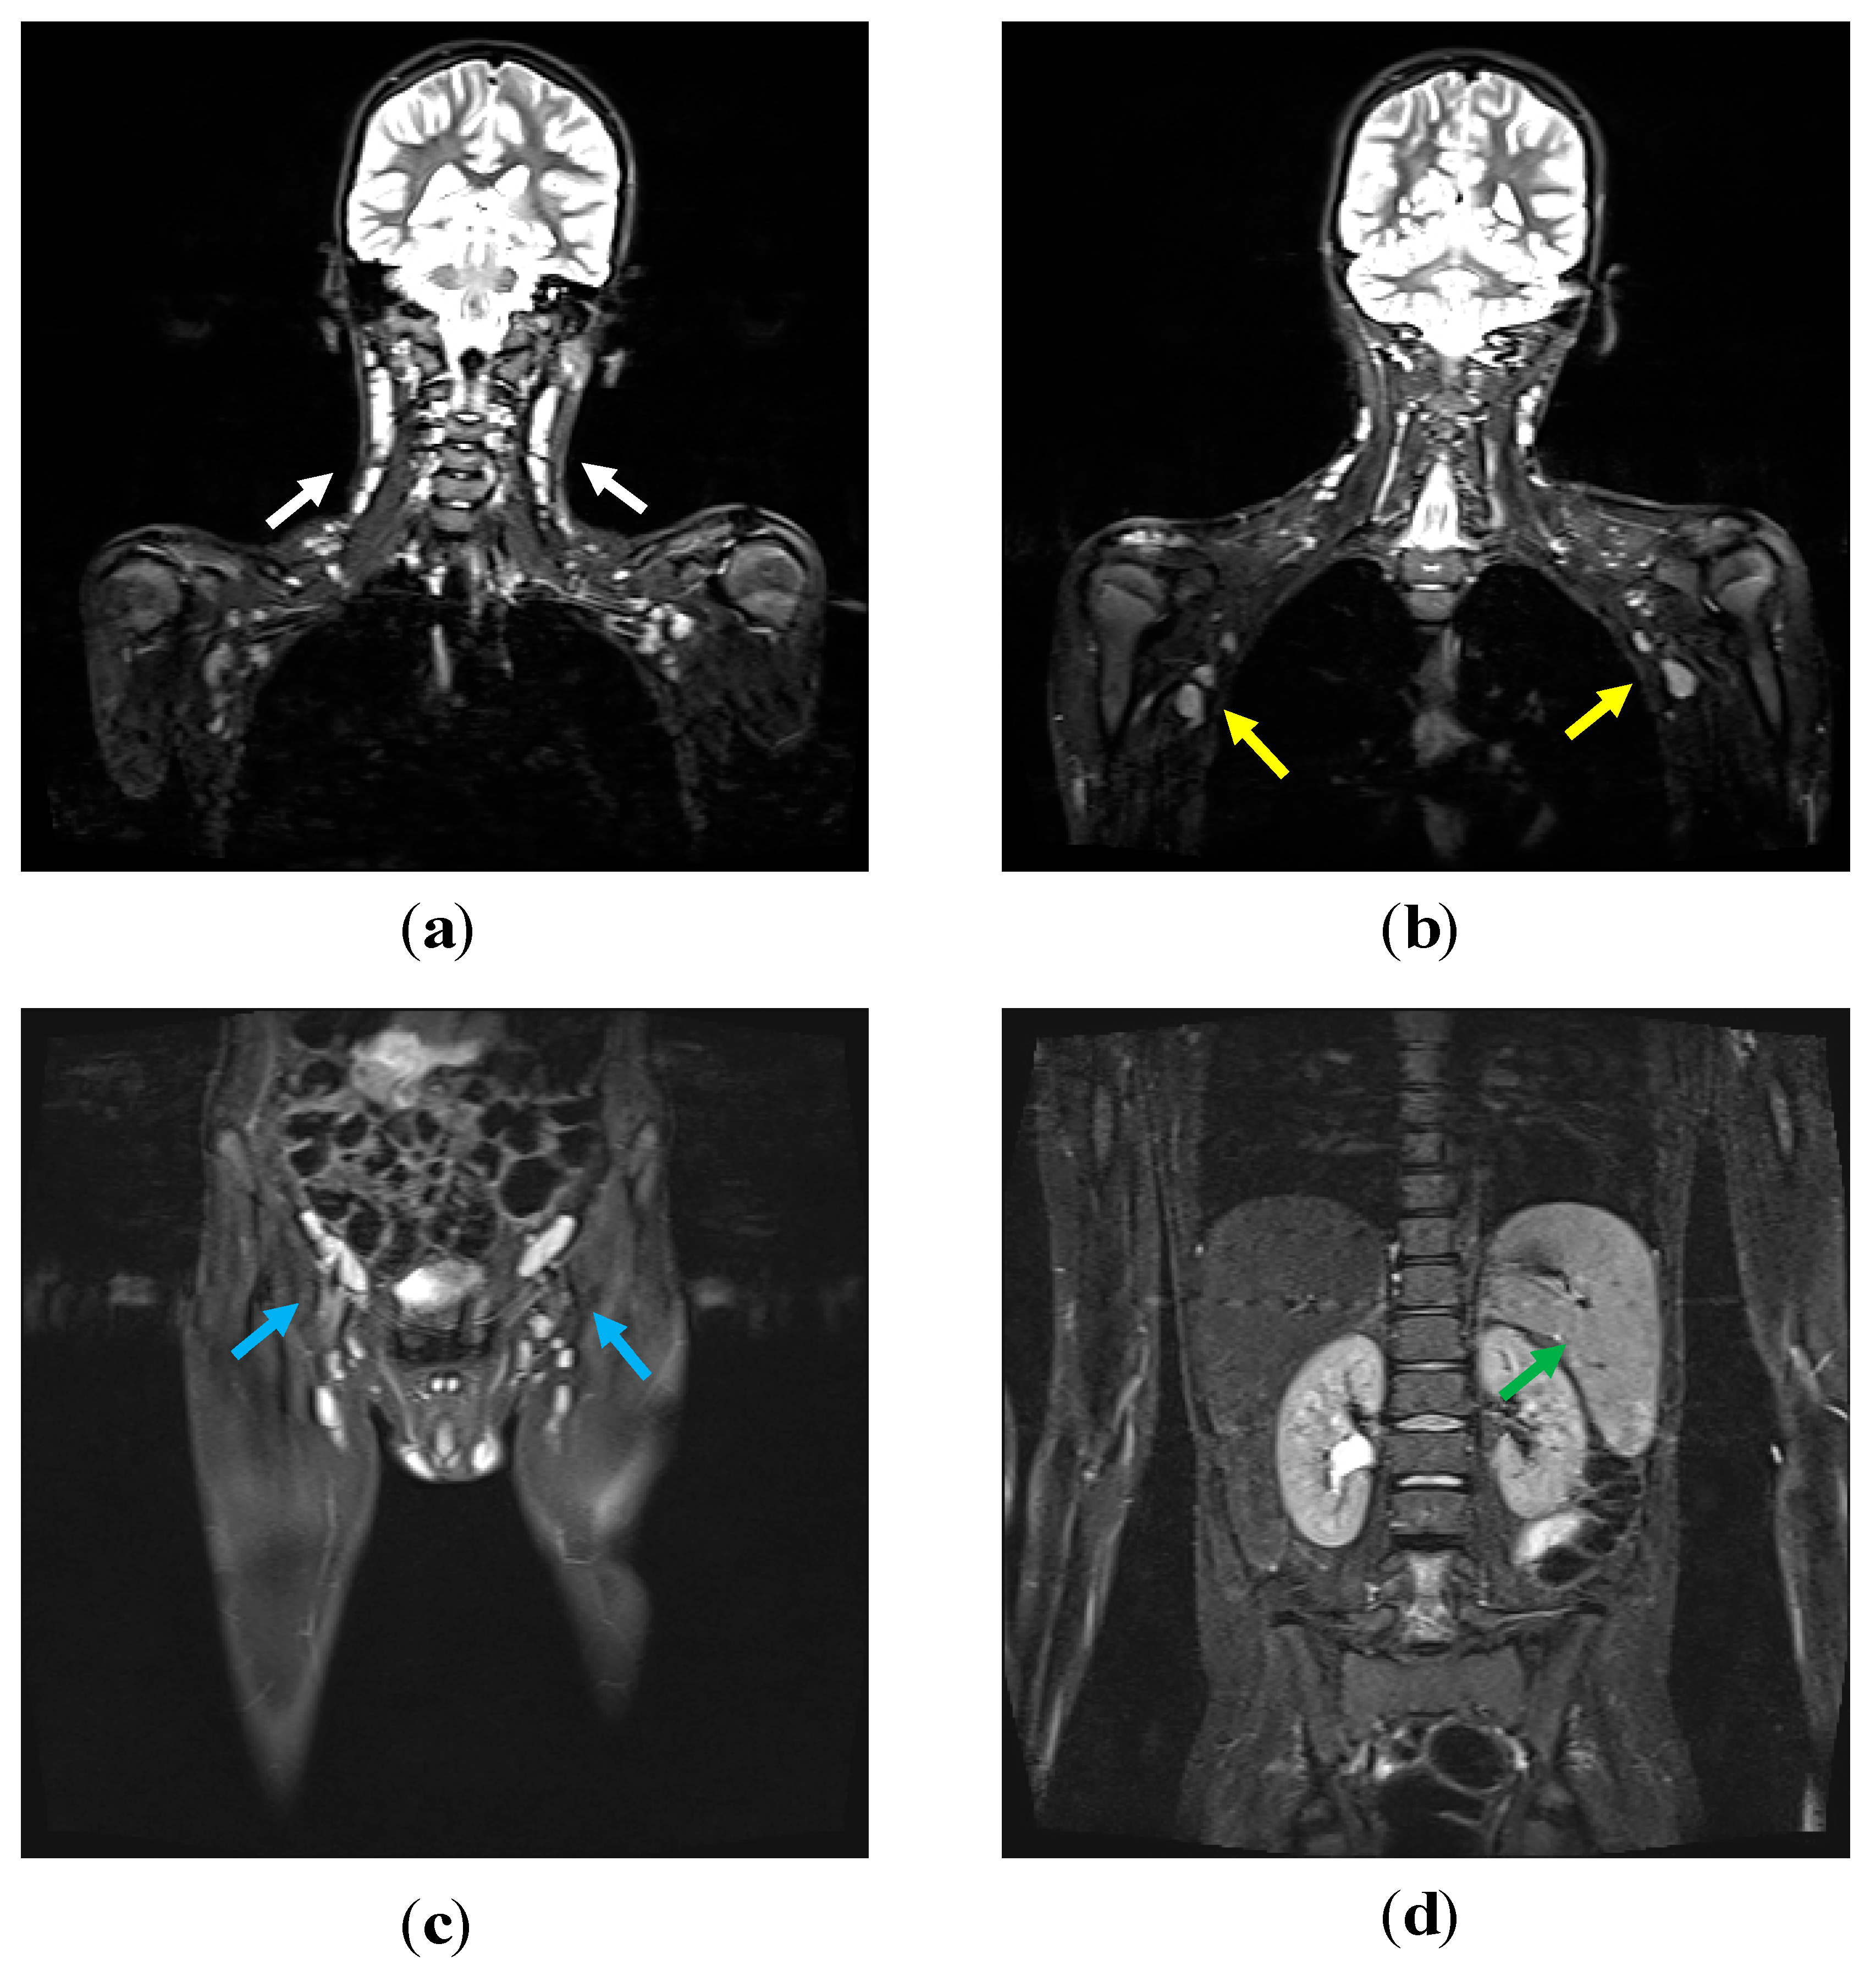

3.3. Lymphoproliferation in APDS-1 Patients